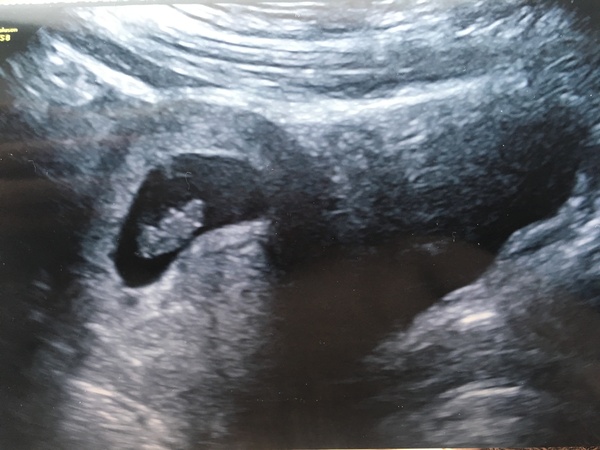

Here she is! I’m just going to refer to her as she until I’m proven wrong. Gut instinct, two previous DD’s, no boys in 27 years and a heartbeat at 171 says girl so it’ll do! Only 8 weeks to find out for sure Grin

Here was my 8w scan - although measuring 3 days behind where I thought I was. We did the heartbeat but they wouldn’t tell us the bmp, boo!

Hoping the 10 week scan will be even better as you say Sals! 😃